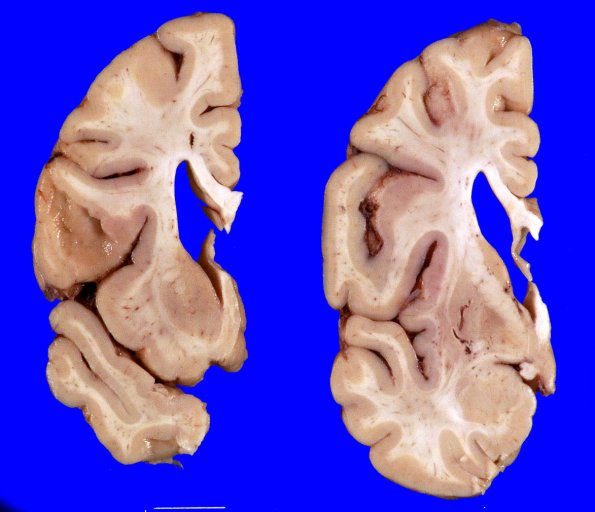

Coronal slicing revealed moderately dilated lateral ventricles and flattened caudate nuclei.